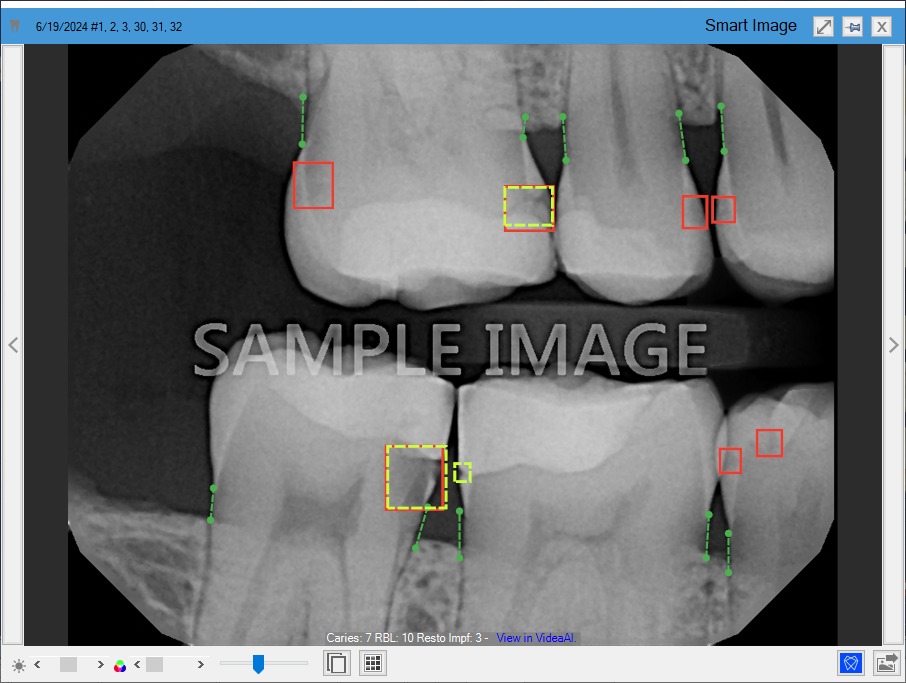

Detecting caries in the enamel (dotted line yellow rectangles) and dentin (solid line red rectangles) on all primary and secondary teeth of patients three years and older. This eliminates the need for manual analysis of all primary and secondary teeth, saving you and your hygienists time.

Measuring interproximal Radiographic Bone Levels in bitewings and Periapical Radiographs (PAs) for patients who are at least 12 years old. Bone level detection is only possible with mesial and distal surfaces. RBL measurements appear as green, yellow, orange, or red dotted lines.

Detecting restoration imperfections in patients 22 years and older by identifying imperfect crown and filling margins and voids. A restoration imperfection is indicated by a yellow rectangle.

In Figure 2, caries are indicated by red rectangles, RBL is indicated by vertical dotted lines, and restorative imperfections are indicated by yellow rectangles and squares.

Figure 2. Diagnostic Viewer with Dentrix Detect AI indications.